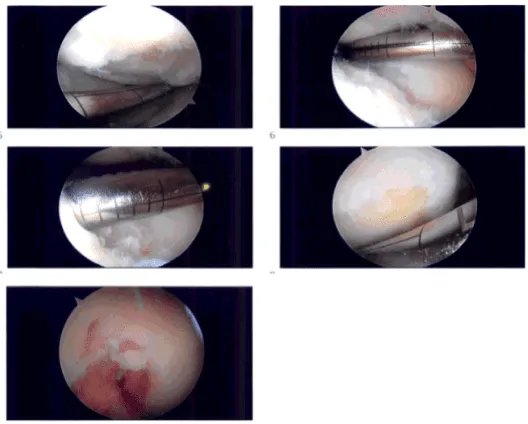

El torniquete se elevó a 250 mmHg. Tras la exsanguinación se realizó una incisión. Se administró anestesia lateral portal. Se realizó una incisión portal anterior medial con el uso de una aguja espinal. Había artritis a lo largo del cóndilo femoral medial y la meseta tibial medial. El menisco estaba intacto.

Hubo un defecto de grado IV en el cóndilo femoral medial que se desbridó con el uso de cureta y se desbridó y se realizó condroplastia por abrasión con el uso de una cureta. El defecto fue medido y medía 1,5 cm por 1,5 cm.

El examen reveló un ligamento cruzado anterior intacto. El examen señaló que el compartimento patelofemoral del tendón tibial lateral mostró cartílago intacto. El examen del compartimento patelofemoral mostró cartílago intacto sobre la rótula, pero había una lesión osteocondral de grado III a IV de la troclea.

El desbridamiento de esta lesión se realizó hasta márgenes estables. El defecto se midió en 1,5 cm x 1 cm. Se tomaron todas las mediciones. Todas las fotos fueron tomadas y guardadas. La rodilla estaba drenada. El cierre se hizo con nylon 3-0.

Imágenes intraoperatorias